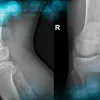

Management of Total Knee Arthroplasty in Post-Traumatic Malunion with Severe Deformity

The objective of this clinical case is to discuss the different therapeutic options for managing knee osteoarthritis associated with severe li…

4th March 26

Management of Total Knee...

The objective of this clinical case is to discuss the differ…